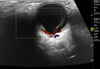

Anatomía ecográfica ocular

Anatomía ecográfica del ojo

Arteria central de la retina